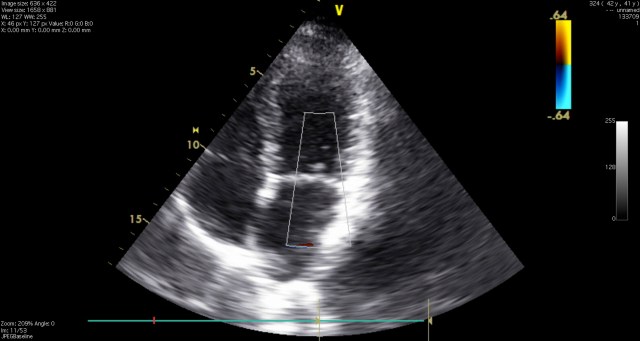

The echocardiogram technician dressed in the same battle gear as those who administered my stress test. She led me into an examining room where I was asked to take my shirt off and lay on the exam room table. An echocardiogram is similar to an Ultrasound conducted on pregnant women but instead of looking for a fetus they are examining the structures of the heart. My inverted t-wave might indicate structural issues with my pump that would not show up during a stress test such as blocked coronary arteries, misfunctioning valves, or other things that thump thump in the chest. From a physical point of view, it is gentle on the patient. All that is required of you is to lay there and occasionally breathe while the technician manipulates a lubed probe across your chest and side. Despite, the fact that the hardest thing that I have to do during the test is to look at an amateurishly drawn sky on the ceiling, I am nervous. What will this test reveal? We know that my heart is functioning well but is there a defect inside ? Am I okay?